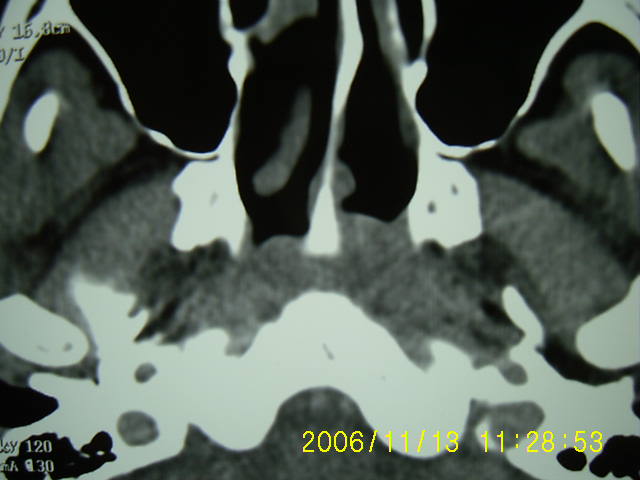

以下是引用zyx168在2006-11-13 13:15:00的发言:[br]左侧咽隐窝变浅,咽后壁软组织(头长肌)肿胀,左侧咽旁间隙推移变小.[br]结合临床,双侧颈部淋巴结肿大,考虑为左侧鼻烟癌.

以下是引用刘明在2006-11-13 12:47:00的发言:[br]左侧咽后壁软组织肿块,咽隐窝消失,首先考虑鼻咽癌